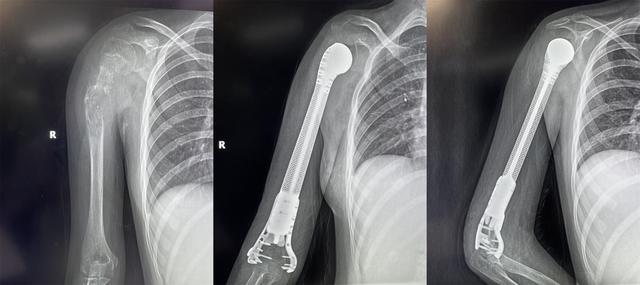

13歲少女患骨肉瘤面臨截肢,3D打印肱骨假體治療成功保肢

2022年4月19日,獲悉,西安市紅會醫(yī)院骨病腫瘤科為一名13歲小患者成功實(shí)施了肱骨惡性腫瘤切除3D打印假體重建術(shù)。165751qartxm1zze19w2ha.jpg

小欣(化名)因右肱骨中上段腫瘤,飽受疾病折磨,幾經(jīng)輾轉(zhuǎn)后來到西安市紅會醫(yī)院就醫(yī),活檢確診為 右肱骨中上段骨肉瘤 。

骨病腫瘤科楊團(tuán)民主任介紹,骨肉瘤是一種好發(fā)于兒童長骨的骨端高度惡性的原發(fā)性腫瘤,治療原則為手術(shù)結(jié)合化療、放療綜合治療。 由于腫瘤范圍較大沒有生物重建可能,也沒有相關(guān)腫瘤假體,保肢難度很大,一直是業(yè)內(nèi)難題,所以普遍選擇截肢。 165751f8i13tpusqaqduut.jpg

對于一個13歲的女孩來說,截肢必然會對孩子的心靈帶來巨大陰影,同時小欣父母表達(dá)了強(qiáng)烈的保肢意愿后,最終決定選擇保肢方案。針對小欣的具體病情,骨病腫瘤科楊團(tuán)民主任帶領(lǐng)團(tuán)隊(duì)成員王志酬、黃桂林、邵宇雄、李爭爭主治醫(yī)師等人,經(jīng)過認(rèn)真病例討論,決定 新輔助化療后,手術(shù)切除右肱骨骨腫瘤 。發(fā)揮3D打印在骨科領(lǐng)域優(yōu)勢,設(shè)計(jì)個體化3D打印肱骨上段鈦合金假體,結(jié)合人工肩關(guān)節(jié)技術(shù),保留部分正常骨、患肢長度,可實(shí)現(xiàn)肱骨重建。165751kg0sm7xwzxmksk7w.jpg

術(shù)前,經(jīng)精密計(jì)算機(jī)輔助設(shè)計(jì)、影像學(xué)數(shù)據(jù)鏡像反求和鈦合金3D打印,假體的3D打印仿骨小梁端和截骨端可以完美貼合,使骨長入得以實(shí)現(xiàn),達(dá)到生物重建效果。這樣既保留了關(guān)節(jié),也減少假體松動的發(fā)生率。同時空隙結(jié)構(gòu)利于軟組織長入。手術(shù)當(dāng)日,在麻醉科配合下,楊團(tuán)民主任團(tuán)隊(duì)密切協(xié)作、精細(xì)操作,依次完成腫瘤切除、3D打印假體植入、軟組織重建系列操作。歷時3小時,順利完成醫(yī)院首例3D打印肱骨假體治療肱骨骨肉瘤手術(shù)。

目前,小欣全身狀況良好,正在進(jìn)行積極的功能鍛煉,力爭盡早實(shí)現(xiàn)正常生活。